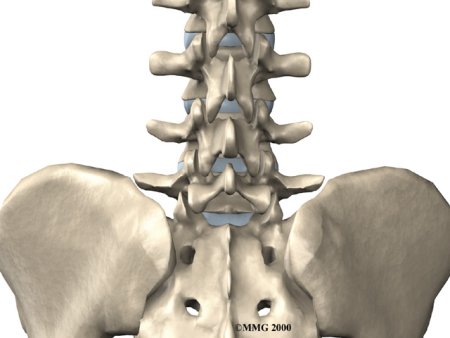

A posterior lumbar fusion is the most common type of fusion surgery for the low back. A fusion is a surgical procedure that joins two or more bones (in this case vertebrae) together into one solid bone. The procedure is called a posterior fusion because the surgeon works on the back, or posterior, of the spine.

Posterior fusion procedures in the lumbar spine are used to treat spine instability, severe degenerative disc disease, and fractures in the lumbar spine.

Surgeons perform this procedure through an incision in the low back. The incision reaches to the , the bony projections off the back of the vertebrae. The surgeon must move aside the muscles along the spine, called the paraspinal muscles. The fusion itself involves the lamina bone, the protective roof over the back surface of the spinal cord. In some cases, the surgeon may enlarge the neural foramina, the tunnels where the nerve roots leave the spinal cord.

The main goal of the spinal fusion (also known as an arthrodesis) is to stop movement of one or more vertebrae. Keeping the fused section from moving helps stop mechanical pain. Mechanical pain occurs when damaged discs and joints that connect the vertebrae become inflamed from excessive motion between the vertebrae. This type of pain is commonly felt in the low back and may radiate into the buttocks and upper thighs.

The spinal nerves are also affected by too much vertebral motion. They begin to rub where they pass through the neural foramina and become swollen and irritated. Also, the neural foramina narrow when a vertebra slides too far forward or backward over the vertebra below. This immediately where they pass through the neural foramina. Nerve swelling, irritation, and pinching produce neurogenic pain. This type of pain often radiates down one or both legs below the knee. Fusion stops this harm to the nerves.